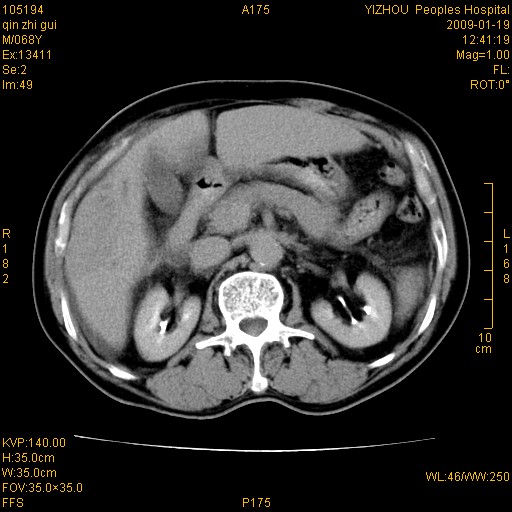

以下是引用随光逐影在2009-1-21 16:11:00的发言:[br]1)考虑肝右叶肝癌并肝静脉及门静脉瘤栓形成。2)肝硬化,少量腹水。3)胆囊炎。4)右侧少量胸腔积液。

病灶外缘凹凸不平,平扫低密度,增强动脉期有强化,门脉早显,静脉期及延期呈延迟强化,结合病史考虑右肝前叶巨块型肝癌可能性大,强化表现不除外胆管细胞癌